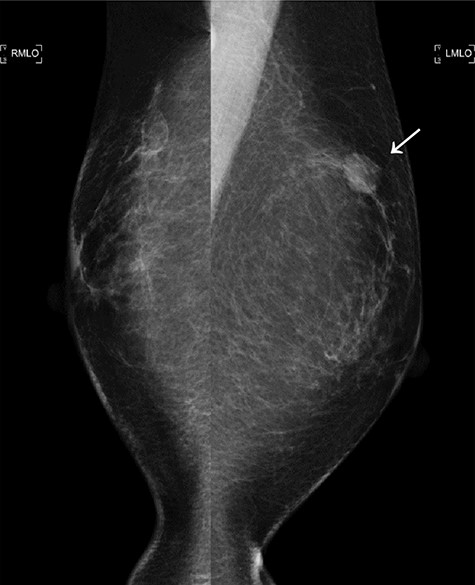

The second mammogram. The mammogram displaying a well-defined borderline high-density mass in the left upper lateral region (arrowhead).